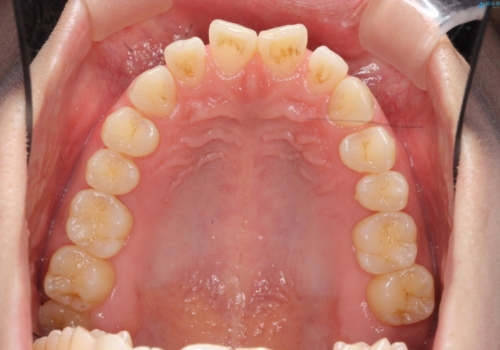

インビザライン で治す 出っ歯の治療

- 前歯の突出感、出っ歯の治療を希望され来院されました。

インビザラインを用いた治療計画を立て、しっかりと出っ歯を治すためにマイクロインプラントを併用します。

マイクロインプラントを併用することでしっかりとマウスピース全体を後方へ引き、前歯の突出感を改善することができました。